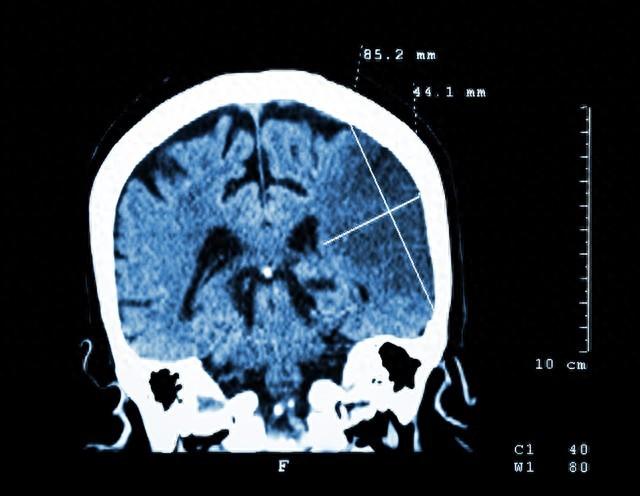

脑梗死的发生是由于大脑血液循环受阻 , 导致的大脑缺血缺氧 , 进而造成局部脑组织坏死引起的脑功能障碍 。 在临床医学中 , 脑梗死的后果非常严重 , 常见症状有脑瘫、偏瘫、言语不清等 。 因此 , 预防脑梗死的发生已成为居家老人必备的常识 。